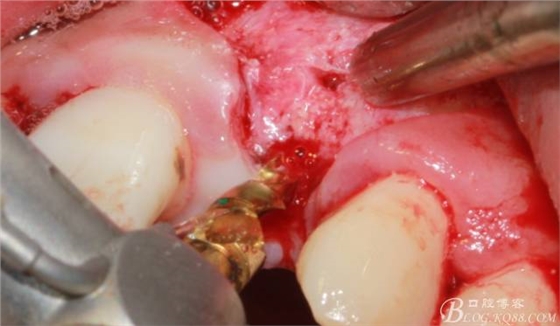

于是我果斷告知患者,手術(shù)失敗了,不能拖延,如不及時處理,炎癥繼續(xù)發(fā)展會很快波及鄰牙牙槽骨。患者接受我的建議。切開翻瓣,骨粉及生物膜消失了,骨吸收嚴(yán)重,幸運的是,因為處理及時,鄰牙骨支持依然存在。

徹底掻刮。